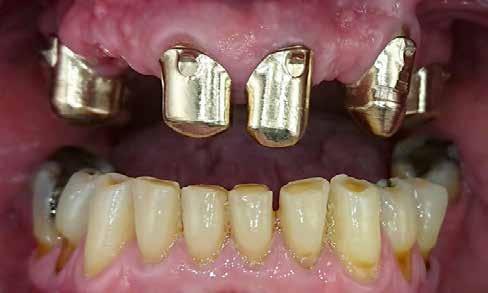

Massimiliano Trombin, dr. Roland Mantsch, Lorenzo Willsch (Németország) 1. a kép 1. kép 2. kép 3. kép

Az egyszárnyú ragasztott híd mellett döntöttünk (1. a kép)

Mivel a szemfogak általában nagyon közel vannak az antagonistához, kettes pótlására a szárnyat inkább a nagymetszőre szoktuk tervezni. Ehhez persze invazív preparációra van szükség – érintetlen fogak esetén ez lehetőleg kerülendő.

A bemutatott esetben azonban könnyen döntöttünk, mivel a szemfog disztális részén nagy tömés volt. A defektust bevontuk az eset megoldásába.